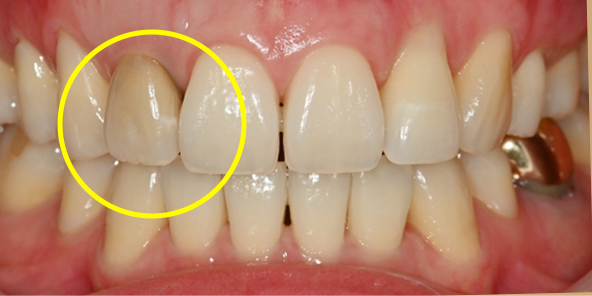

임플란트를 식립하고 동시에 보철물도 완성해드립니다.

내원 당일 이루어지는 임플란트 기술력! 하루 완성 임플란트는 당일에 식립하고

임시 보철물까지 완성됩니다.

일상생활이 가능하도록 임시 보철물 완성